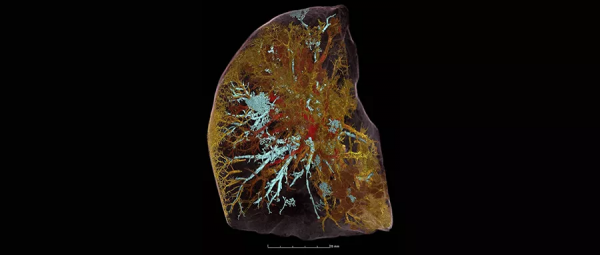

目前這支團隊已透過Hip_ CT,成功觀察到新冠病毒是如何在兩個血管系統之間進行〝血液分流",還掃描一名剛剛死於冠病的54歲男子左肺,鉅細靡遺地呈現出肺部的一切細節,包括末梢的微血管都很具體,其中肺泡呼吸性細支氣管是藍色,開放的血管是紅色,染疫後被閉塞和損壞的血管是黃色。